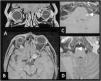

To describe the magnetic resonance imaging (MRI) findings for the most common inflammatory and immune-mediated diseases that involve the brainstem.

ConclusionInflammatory lesions involving the brainstem are associated with a wide range of autoimmune, infectious, and paraneoplastic syndromes, making the differential diagnosis complex. Being familiar with these entities, their clinical characteristics, and their manifestations on MRI, especially the number of lesions, their shape and extension, and their appearance in different sequences, is useful for orienting the radiological diagnosis.